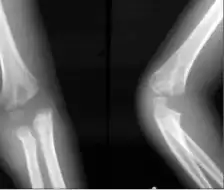

| Cubitus varus versus cubitus valgus | |

Cubitus varus is a varus deformity in which the extended forearm is deviated towards midline of the body.

The "opposite" condition is cubitus valgus.